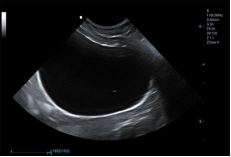

3C5PDS ● 1.0-7.5MHz ● Convex array probe ● For Abdomen and Reproduction |

![]() |